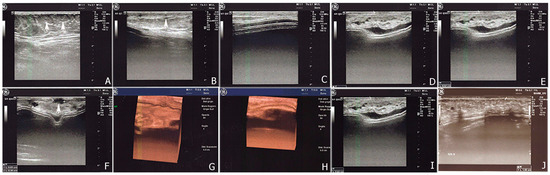

2.2.1. Breast Fat Grafting

2.2.2. Pathological Scar Fat Grafting